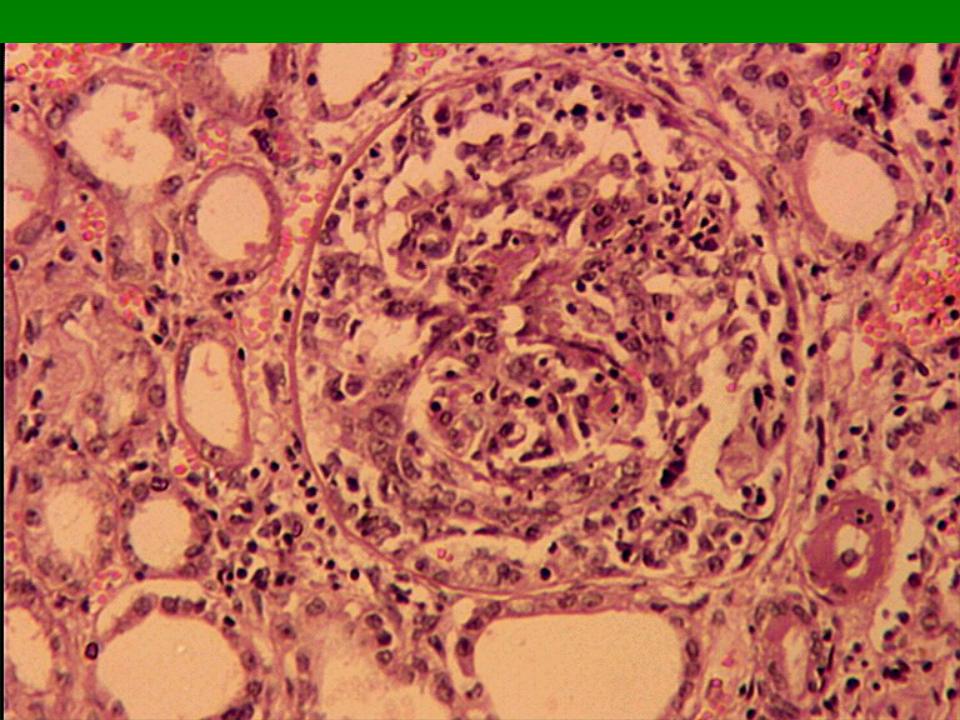

Симптомы подострого гломерулонефрита: фото и описание